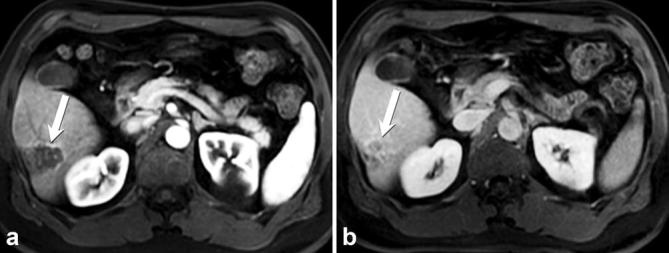

Figure 2.

Flash-filling/capillary haemangioma: axial contrast-enhanced T1 weighted images of a small lesion (arrow). Delayed phase image (a) shows persistent enhancement of the lesion that matches blood pool. In arterial phase (not shown in the figures), the lesion exhibited a rapid homogenous enhancement. Axial T2 weighted image (b) shows increased signal intensity of the lesion typical of a flash filling haemangioma.